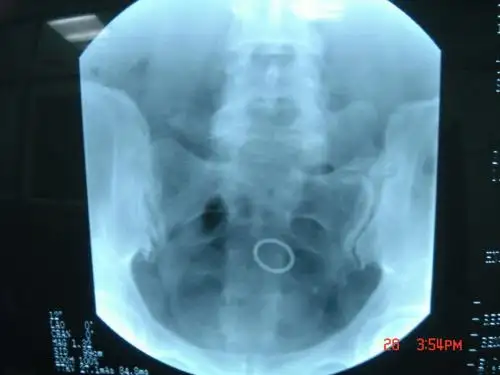

目前应用最广泛的是X射线检查,其穿透力较强,能通过身体各个部位进行检查,并形成相应的影像。

影像学表现主要包括X线片、CT图像、MRI图像等。

由于不同放射线对人体组织的穿透力和反射率不同,所以在影像学表现上也存在差异。

例如,X线片在显示骨头等硬组织方面效果显著,但在显示软组织方面较为有限;而CT图像则相反,可以更好地显示软组织。